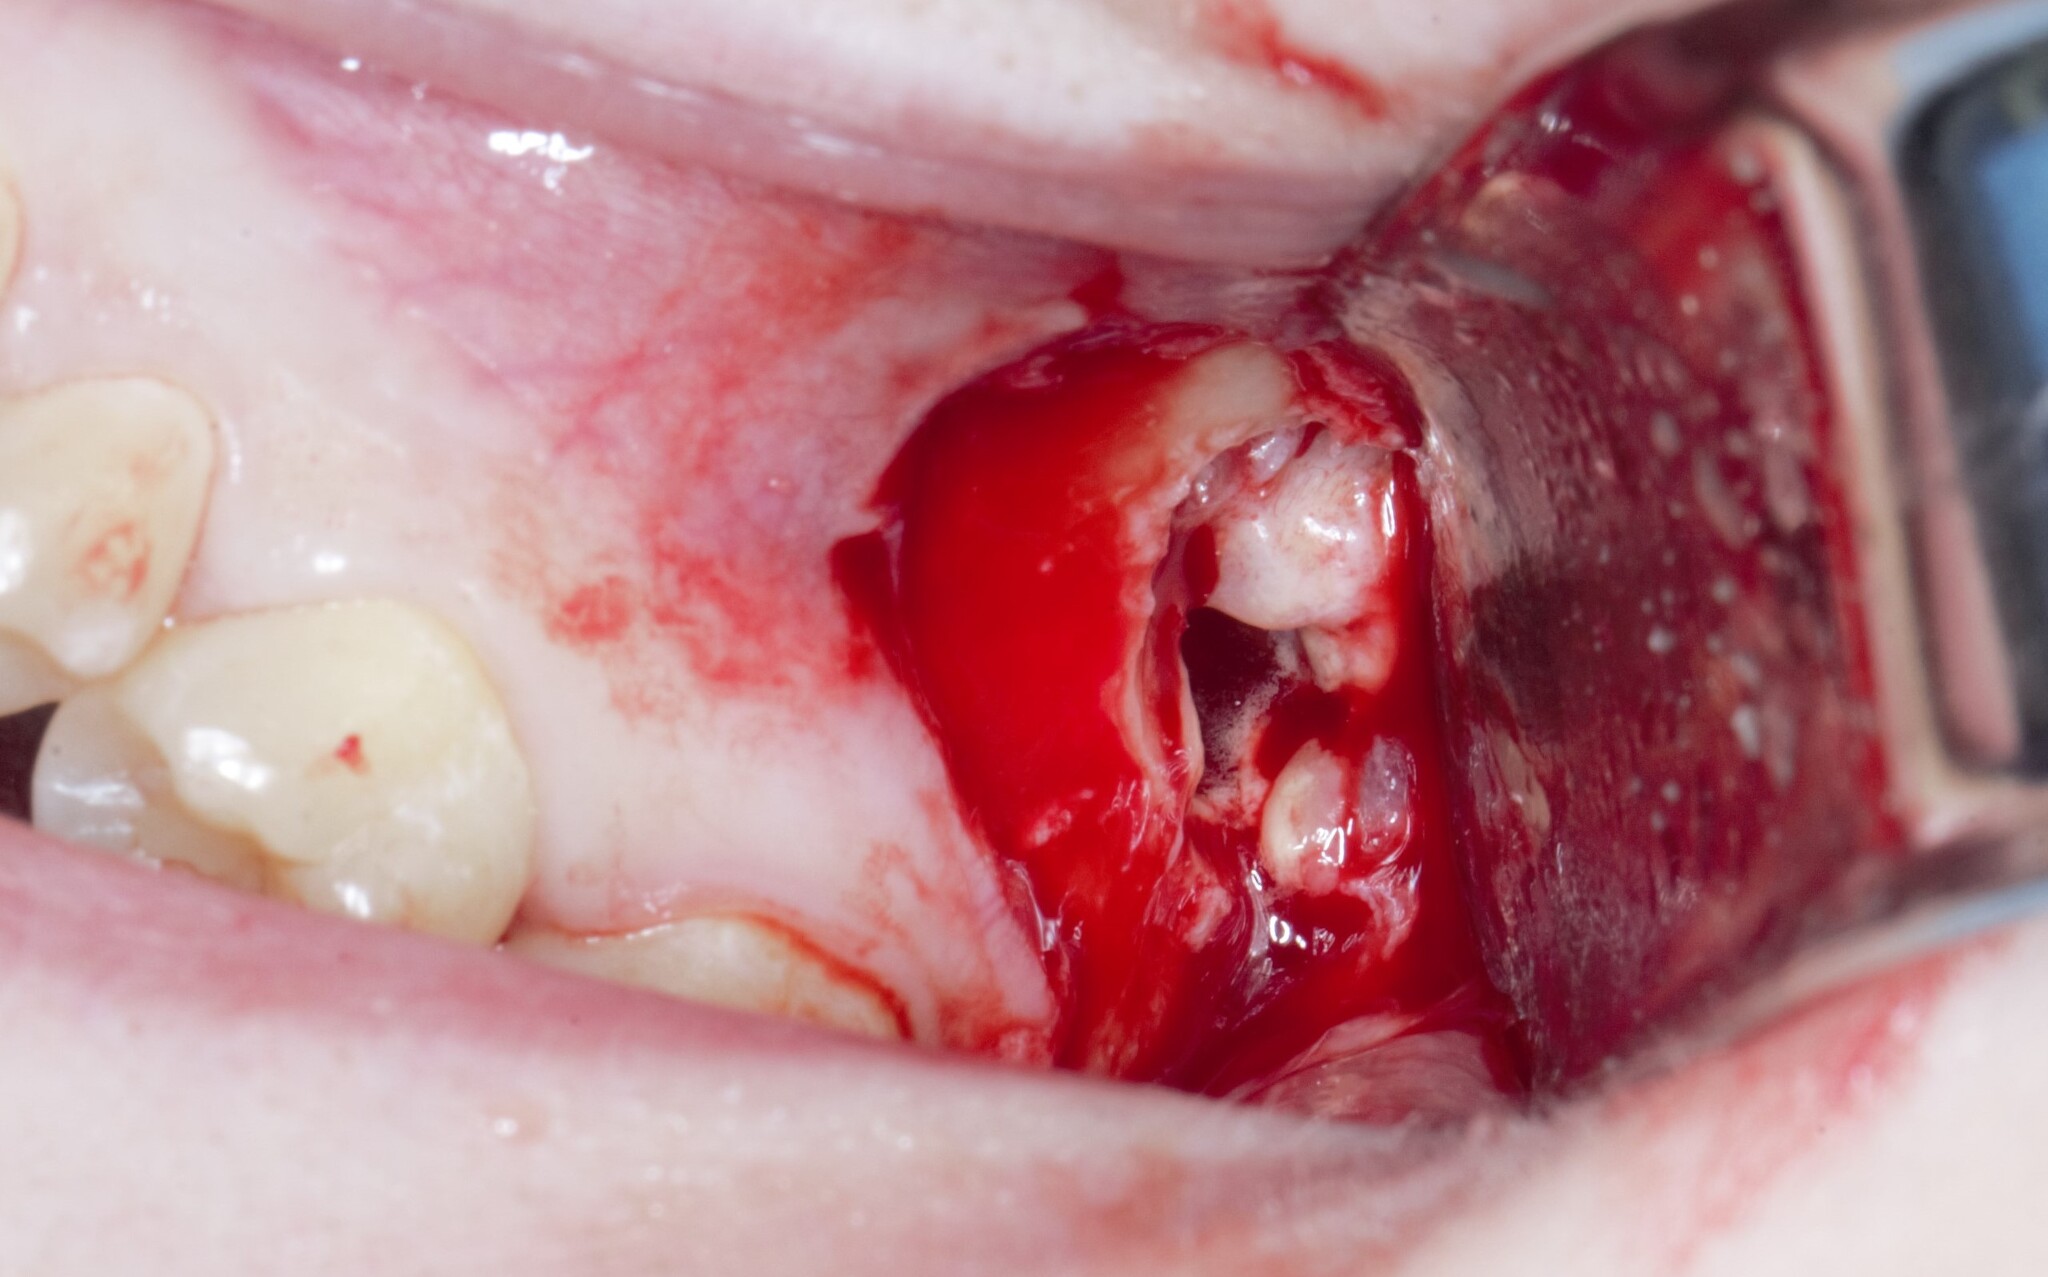

Я сделал анестезию, разрез и отслоил слизисто-надкостнечный лоскут:

Добрался до кости и при помощи специального прямого наконечника и шаровидного бора сделал окошко в проекции верхнечелюстной пазухи и удаляемого зуба мудрости:

Вооон там сверху уже можно увидеть жевательную поверхность зуба (белого цвета).

Понял, что окошко маловато. Немного «расширяемся»:

и начинаем подтягивать зуб при помощи элеватора:

Вот и он «красавчик». Берем зажим и хватаем эту мразоту за хвост, точнее за фолликул и извлекаем: